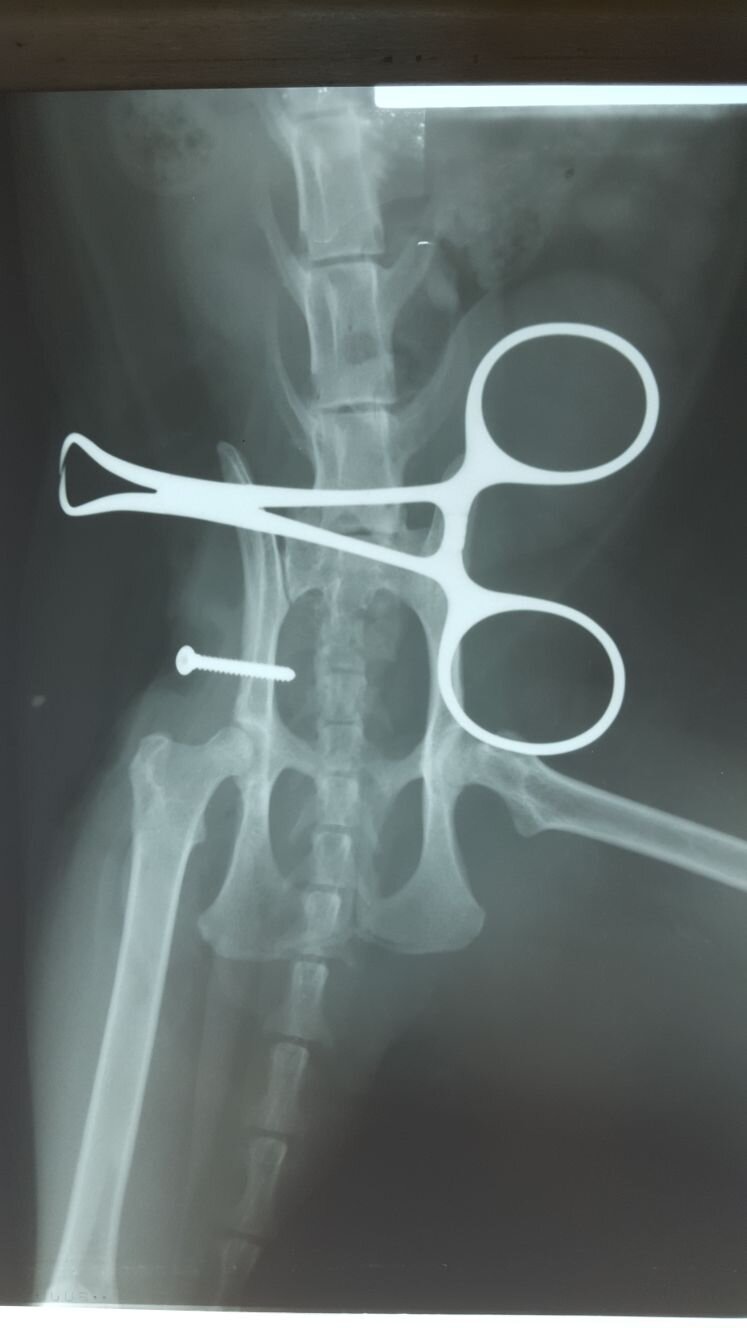

possibile se l ' articolazione non ha perso " il diritto di domicilio" per l ' apposizione nell ' acetabolo di materiale infiammatorio che ne ostacola il riposizionamento, e la stabilizzazione a" cielo aperto" con tecniche chirurgiche (sutura ileofemorale / protesizzazione capsula articolare / protesi capsula con ancorette o viti / Toggle Pin - fissazione con cavigliotto )

La scelta del metodo è in relazione al danno capsulare. Per Perla si è resa necessaria la stabilizzazione chirurgica , le foto mostrano la radiografia prima dell ' intervento, in corso di intervento e la gatta in sesta giornata post intervento. Perla ha iniziato a poggiare correttamente l ' arto a terra in quarta giornata post intervento.